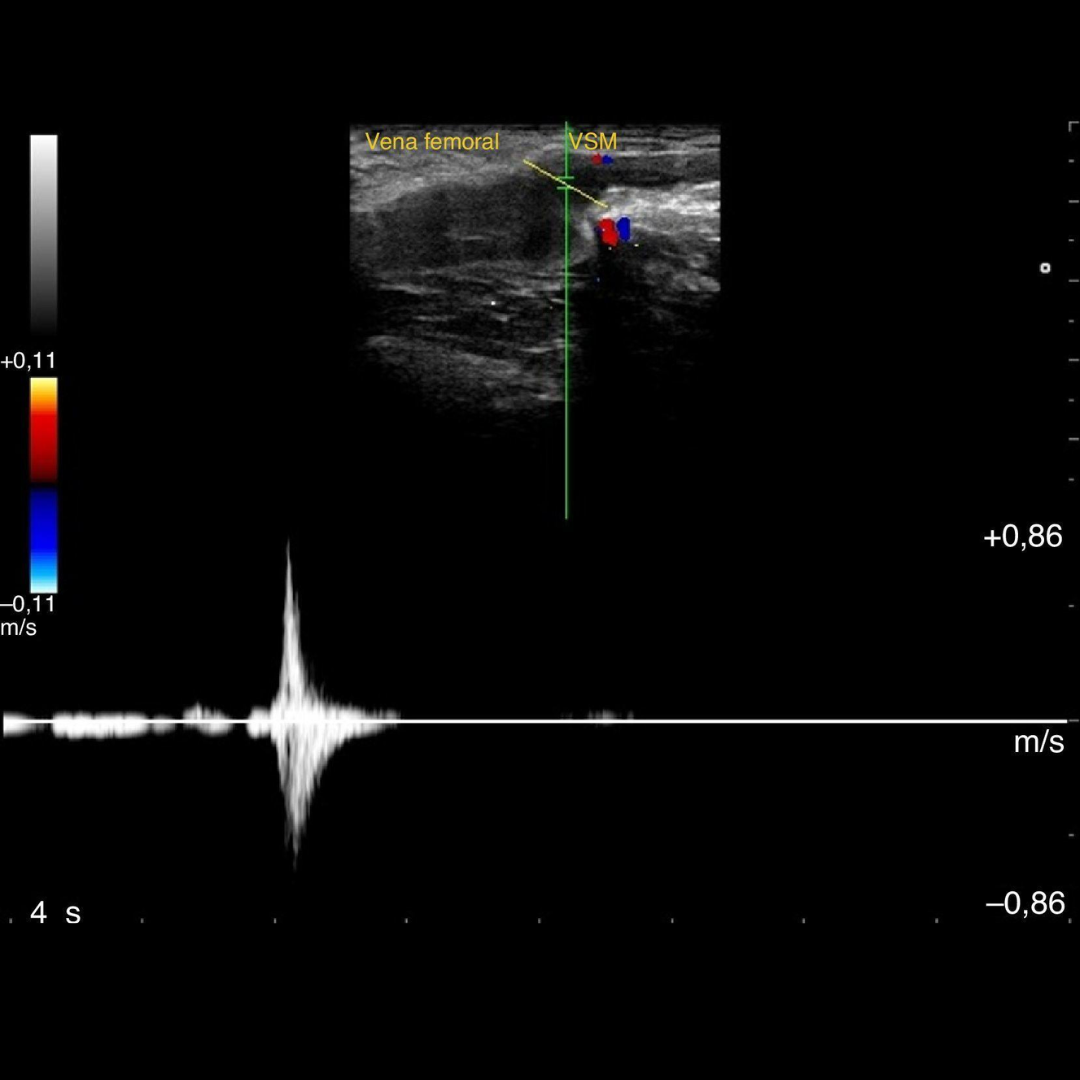

Ecografía Doppler Venoso

La ecografía Doppler Venoso es un estudio importante que permite evaluar las venas de miembros superior e inferiores, y permite evidenciar la presencia válvulas venosas insuficientes que condicionen varices, así como obstrucciones venosas en la trombosis venosa profunda.